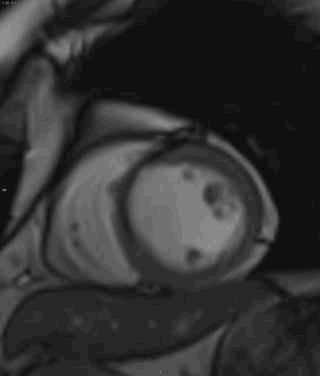

电影短轴位

电影:间隔壁左室中央段-心尖段、左室心尖心肌变薄,心尖膨隆,室壁运动减低,心肌内见低信号

T1WI :间隔壁左室中央段-心尖段心肌内见条形高信号

T2WIFS:间隔壁左室中央段-心尖段、左室心尖心肌内见条形低信号

首过灌注:间隔壁左室中央段-心尖段、左室心尖近乎透壁性灌注减低

LGE:间隔壁左室中央段-心尖段、左室心尖透壁性延迟强化

冠心病,间隔壁左室中央段-心尖段、左室心尖陈旧心肌梗死并

脂肪沉积;左心室心尖部室壁瘤